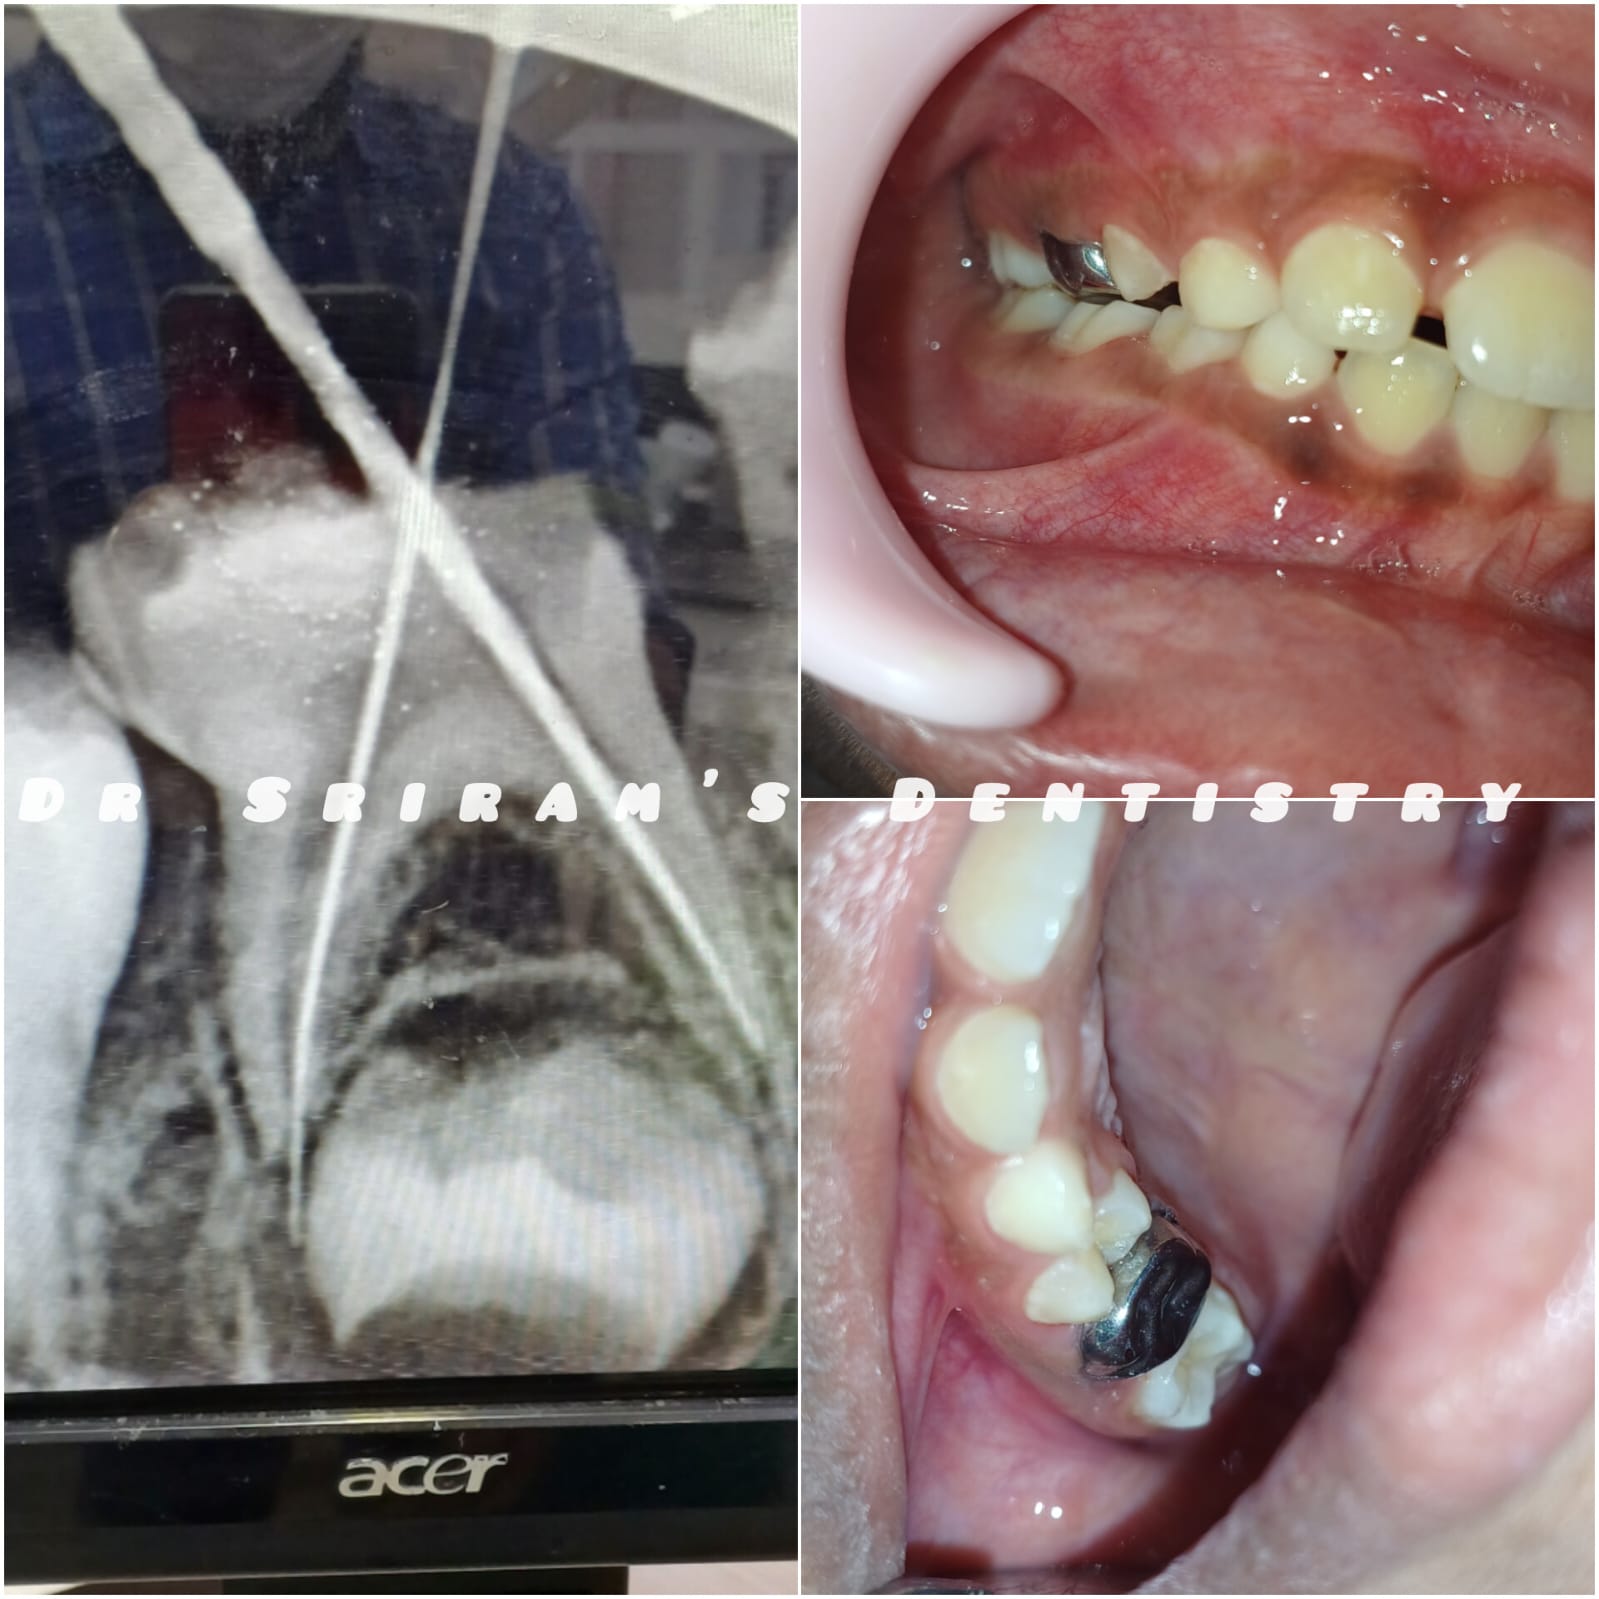

Gallery Home Gallery Pulpectomy Broken File Retrieval Root Canal Treatments Orthodontic Treatments Wisdom Teeeth Removal